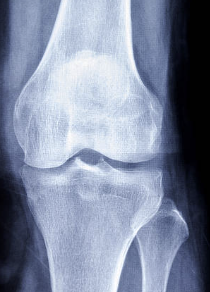

십자인대는 무릎 관절 내부에 있는 4개의 인대 중 하나로, 대퇴골과 승골 사이에 위치해 있습니다. 십자인대는 무릎 관절의 안정성을 유지하는 역할을 담당합니다. 무릎 관절에 직접적인 충격이 가해지거나, 무릎이 강한 스트레스를 받았을 때 십자인대가 손상되는 경우가 있습니다. 이러한 십자인대 손상은 스포츠 활동이나 사고 등으로 발생할 수 있습니다. 십자인대 손상 증상으로는 무릎 통증, 부종, 불안정감 등이 있으며, 심한 손상의 경우 수술이 필요할 수도 있습니다. 십자인대 손상을 예방하기 위해서는 적절한 스포츠화를 착용하고, 몸을 충분히 기르며, 스포츠를 할 때 안전장비를 착용하는 것이 중요합니다.

무릎 십자인대 파열 원인

무릎 십자인대 파열의 원인은 여러 가지가 있습니다. 주요 원인은 다음과 같습니다.

- 외상: 스포츠 활동이나 교통사고 등으로 인한 외상이 가장 흔한 십자인대 파열 원인입니다. 갑작스러운 충격이나 굽히는 움직임 등으로 인해 십자인대에 손상이 생길 수 있습니다.

- 급격한 움직임: 무릎을 급하게 움직이는 스포츠나 활동에서 십자인대 손상이 발생할 수 있습니다. 예를 들어 빠르게 방향을 바꾸거나, 높이 뛰어내리는 등의 움직임이 그 예입니다.

- 나이: 연령이 들면 십자인대의 강도가 약해지기 때문에 십자인대 파열 위험이 높아집니다.

- 유전적 요인: 가족력에 십자인대 손상이 있을 경우, 개인이 십자인대 파열을 경험할 위험이 높아집니다.

- 과도한 운동: 과도한 운동이나 특정한 스포츠 활동을 하면 십자인대가 과도하게 사용되기 때문에 파열될 위험이 높아집니다.

무릎 십자인대 파열의 원인은 다양합니다. 이러한 원인들을 최대한 예방하고, 적절한 안전장비를 착용하며, 몸을 충분히 준비하고 운동하는 것이 중요합니다. 만약 십자인대 손상이 의심되면 전문의와 상담하여 적절한 치료를 받는 것이 중요합니다.

무릎 십자인대 파열 치료방법

무릎 십자인대 파열의 치료 방법은 파열의 정도와 위치에 따라 다릅니다. 대개는 무릎의 안정성을 유지하고, 염증을 감소시키고, 근력을 강화하는 것이 중요합니다. 주요한 치료 방법은 다음과 같습니다.

- 보존적 치료: 가벼운 십자인대 손상의 경우, 보존적 치료로 치유가 가능합니다. 냉찜질, 압박, 높이끌기 등의 보존적 치료를 통해 증상을 완화시키고, 무릎 관절을 안정시키는 운동을 하며 근력 강화 운동도 진행합니다.

- 물리치료: 물리치료는 십자인대 손상 치료에 매우 효과적입니다. 전기 치료, 초음파 치료, 마사지, 스트레칭 등을 포함합니다. 이러한 물리치료를 통해 염증을 감소시키고, 근력을 강화하여 무릎 관절의 안정성을 유지할 수 있습니다.

- 수술: 무릎 십자인대 파열이 심한 경우 수술이 필요할 수 있습니다. 수술은 보통 파열된 십자인대의 종류와 위치에 따라 다릅니다. 일반적으로 파열된 십자인대를 고정하고, 다른 인대 조직으로부터 이식을 하는 방법이 사용됩니다.

무릎 십자인대 파열 치료는 환자의 상태와 십자인대 손상의 정도에 따라 다릅니다. 가벼운 손상의 경우에는 보존적 치료와 물리치료만으로도 치유가 가능합니다. 하지만, 중등도 이상의 십자인대 파열은 치료하지 않으면 더 심한 부상을 초래할 수 있으므로, 적절한 치료가 필요합니다. 무릎 십자인대 파열 치료는 전문적인 전문의의 진단과 조언을 따르는 것이 중요합니다.